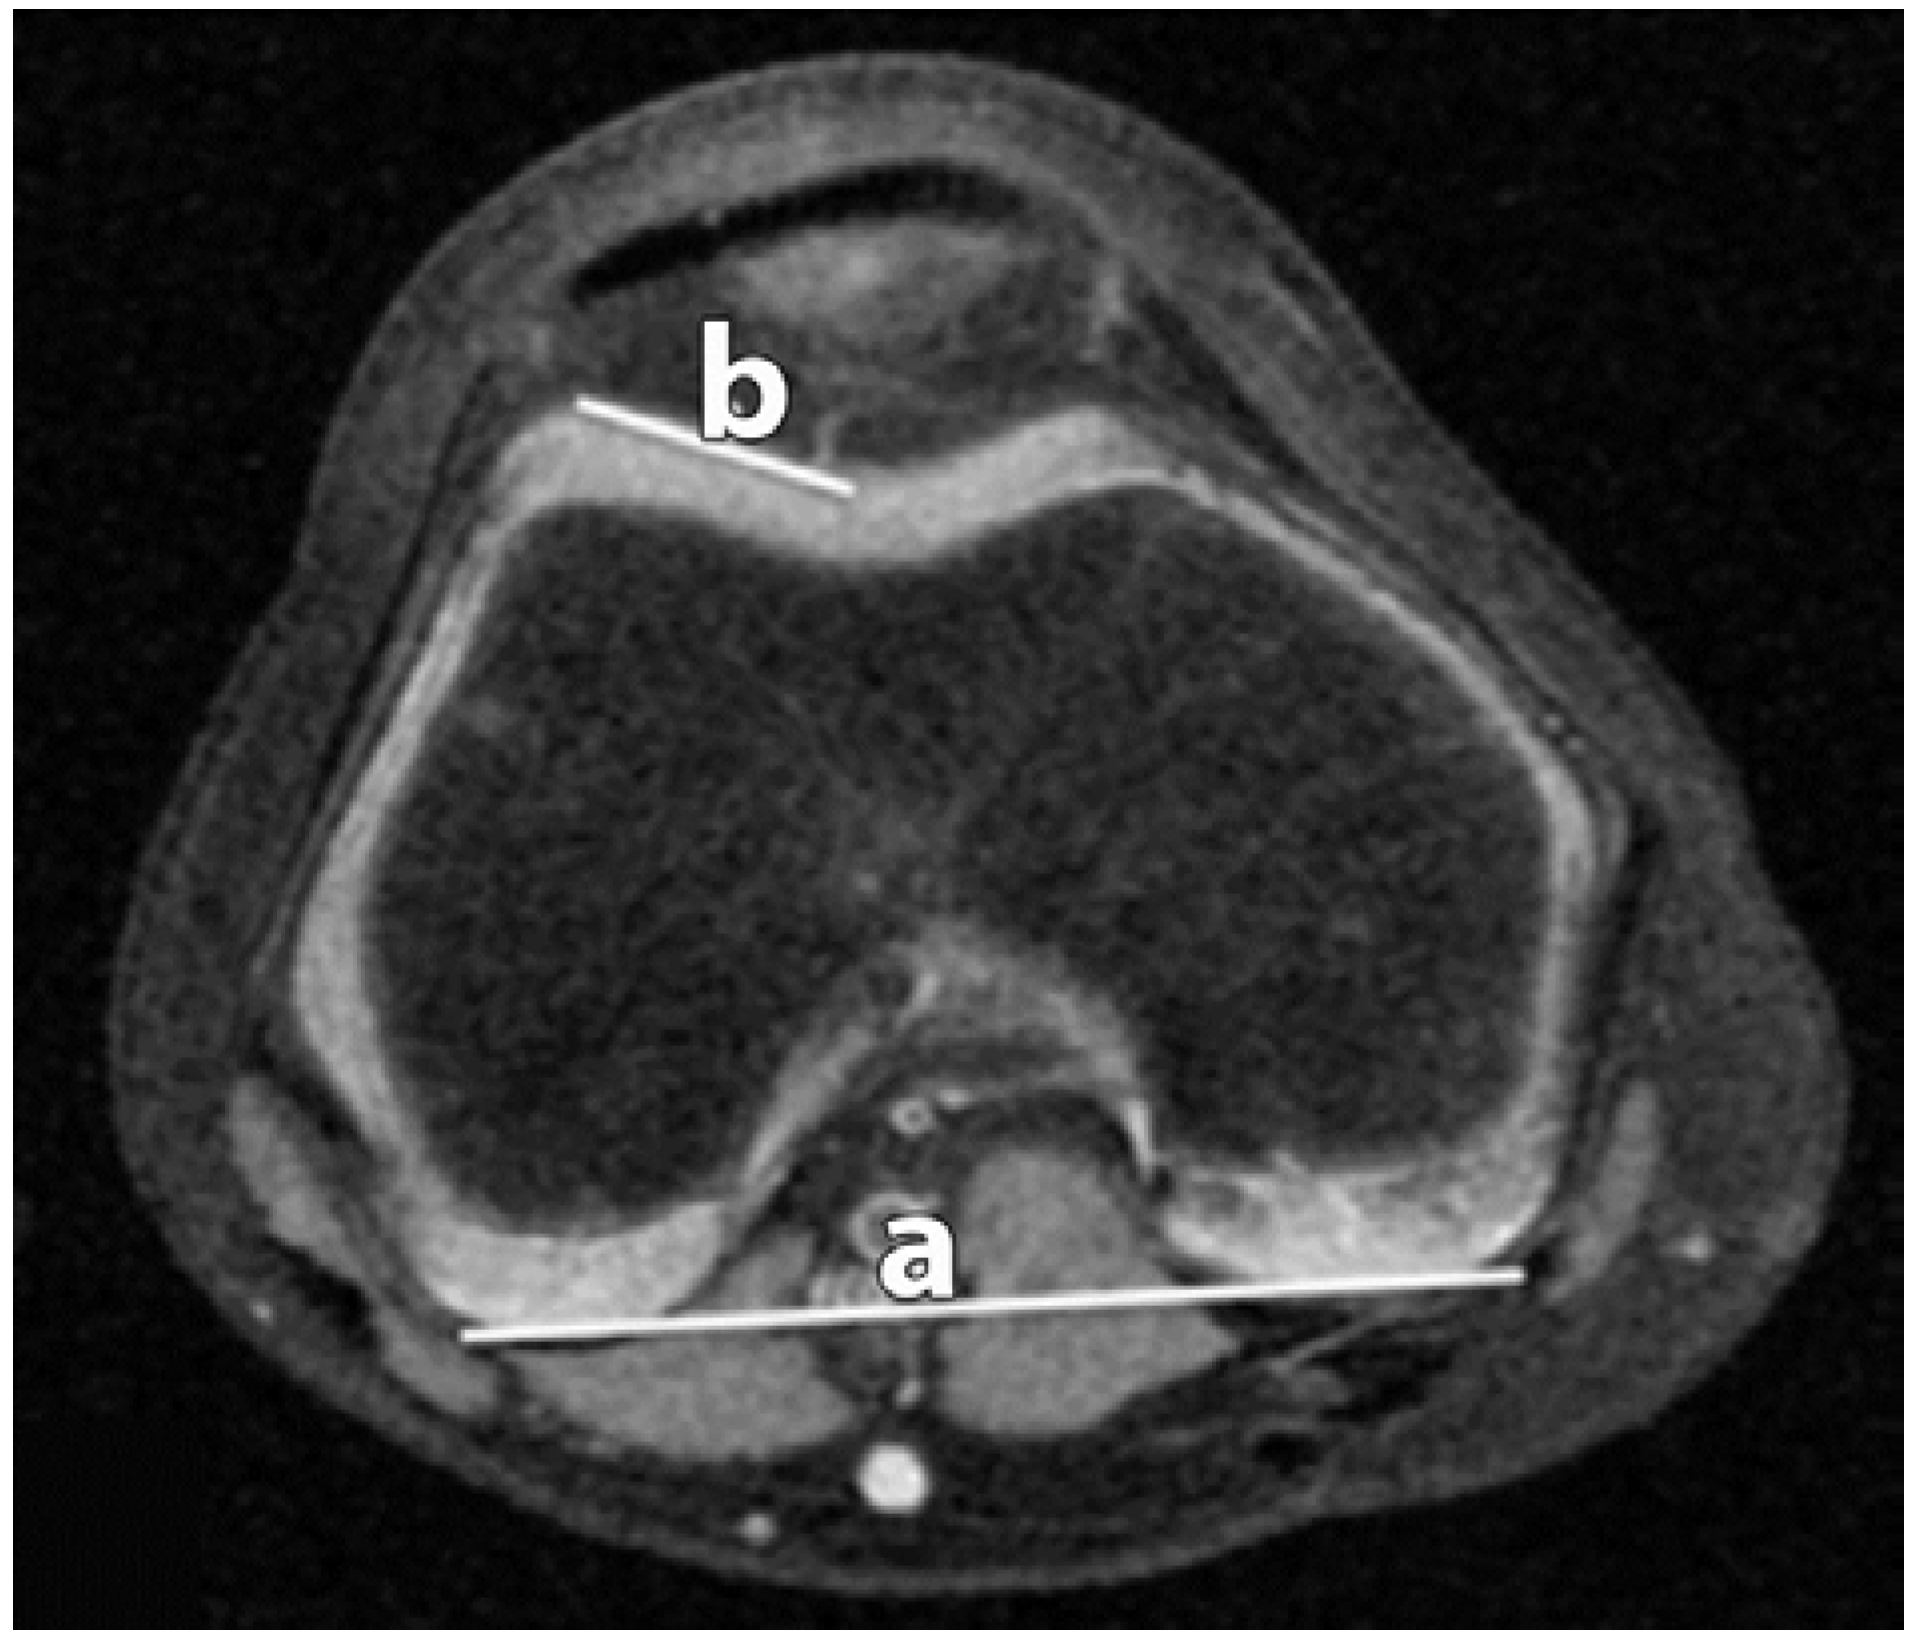

Figure 1.

Lateral Trochlear Inclination (LTI). The angle between the lateral trochlear facet (b); and the line along the posterior condyles (a) is measured.